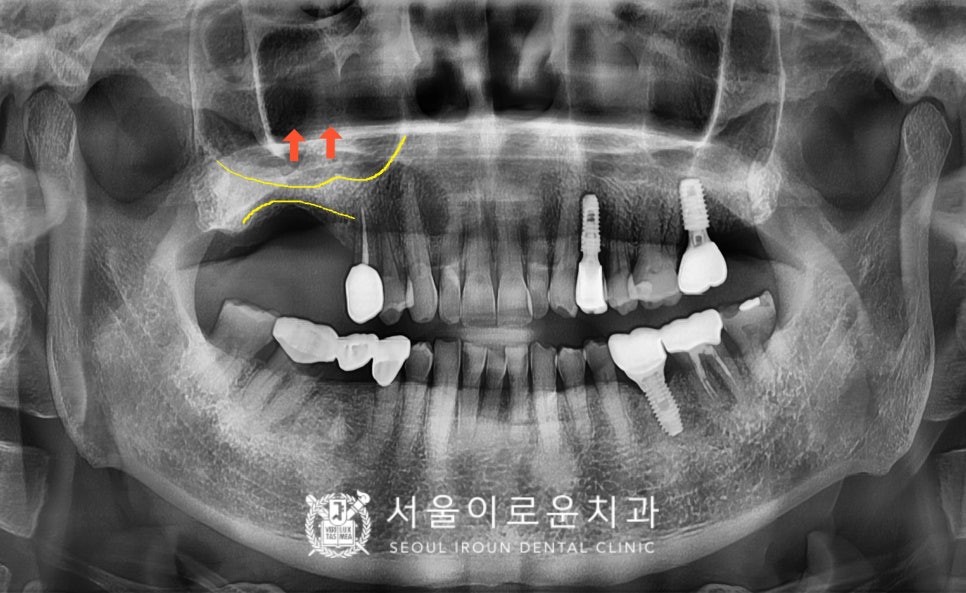

위턱의 오른쪽 어금니 부위에는

상악동 거상술을 동반한

임플란트 식립을 진행하였는데요.

상악동은 아주 얇은 막의

공기주머니이기 때문에

들어 올리는 과정에서

손상이 가지 않도록 주의하며

섬세한 스킬로 수술을 도와드렸습니다.

술 후 파노라마와 3D-CT를 통해

발치 후 즉시 임플란트와

상악동 거상술을 동반한 임플란트가

안정적으로 식립된 것을 체크하였답니다.